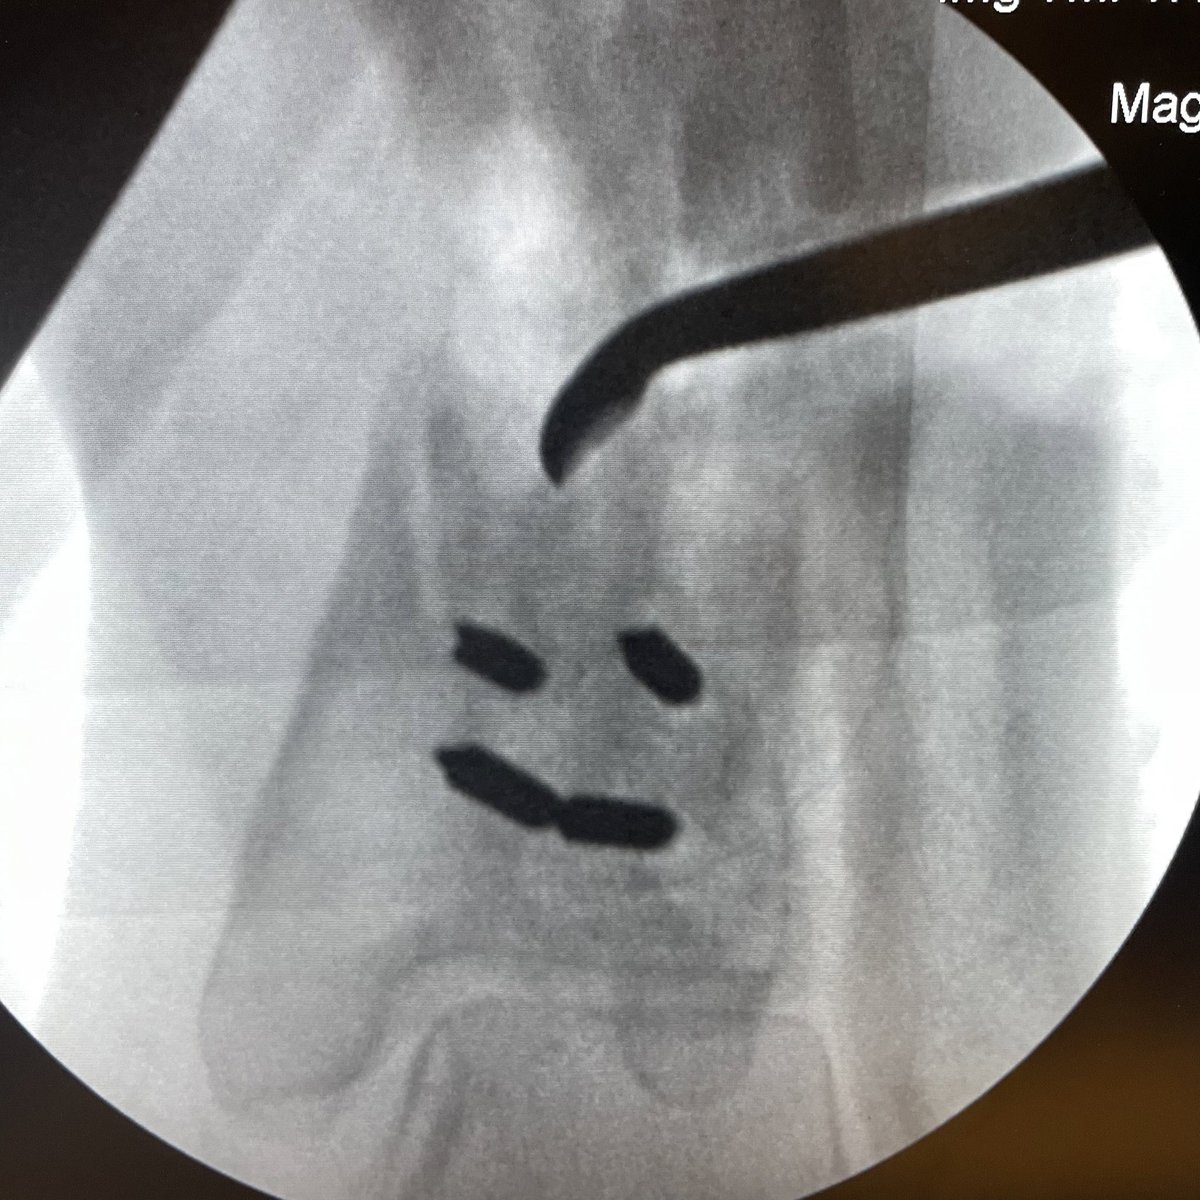

Nonunion repair making me AND this bone happy!!😂😂😊😊👍👍#orthotwitter #OTA #limblengthening #nonunion

JanetConwayy's tweet image. Nonunion repair making me AND  this bone happy!!😂😂😊😊👍👍#orthotwitter #OTA #limblengthening #nonunion